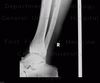

No vypadalo to dobře kolo celý já taky celej,jel jsem dál. Po nějaký době jsem však zjistil že pravá noha začíná otékat a je značně citlivější. No říkal jsem si modřina co se dá dělat. Jezdil jsem ještě další 2–3 hodiny a pak domů. Druhý den už však přišla opravdu bolest,na nohu jsem nemohl došlápnout ,ale odchodil jsem ještě celý den v práci.V pátek ráno jsem si vydal k doktoroj a hned na rentgen. Kde bylo zjištěno , že mám zlomený talus konkrétně (processus posteriot tali). Sádru jsem však nedostal jen takovou tu ortézu.